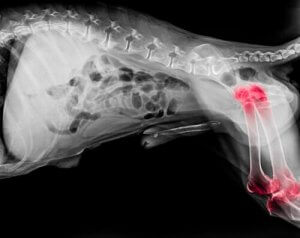

Experts believe that approximately one in five dogs is suffering from arthritis. While this joint condition can appear at any age, it’s more common in older dogs. Broadly speaking, arthritis is a degenerative disease which causes inflammation of both the elbow and shoulder joints.